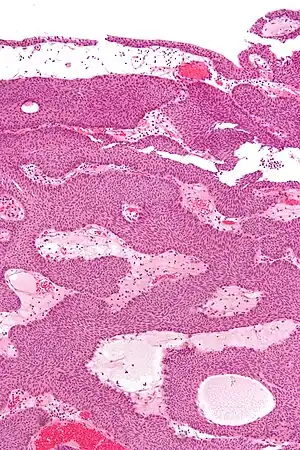

Histopathology representing an inverted papilloma of the urinary bladder that was cystoscopically resected. Hematoxylin and eosion stain. -